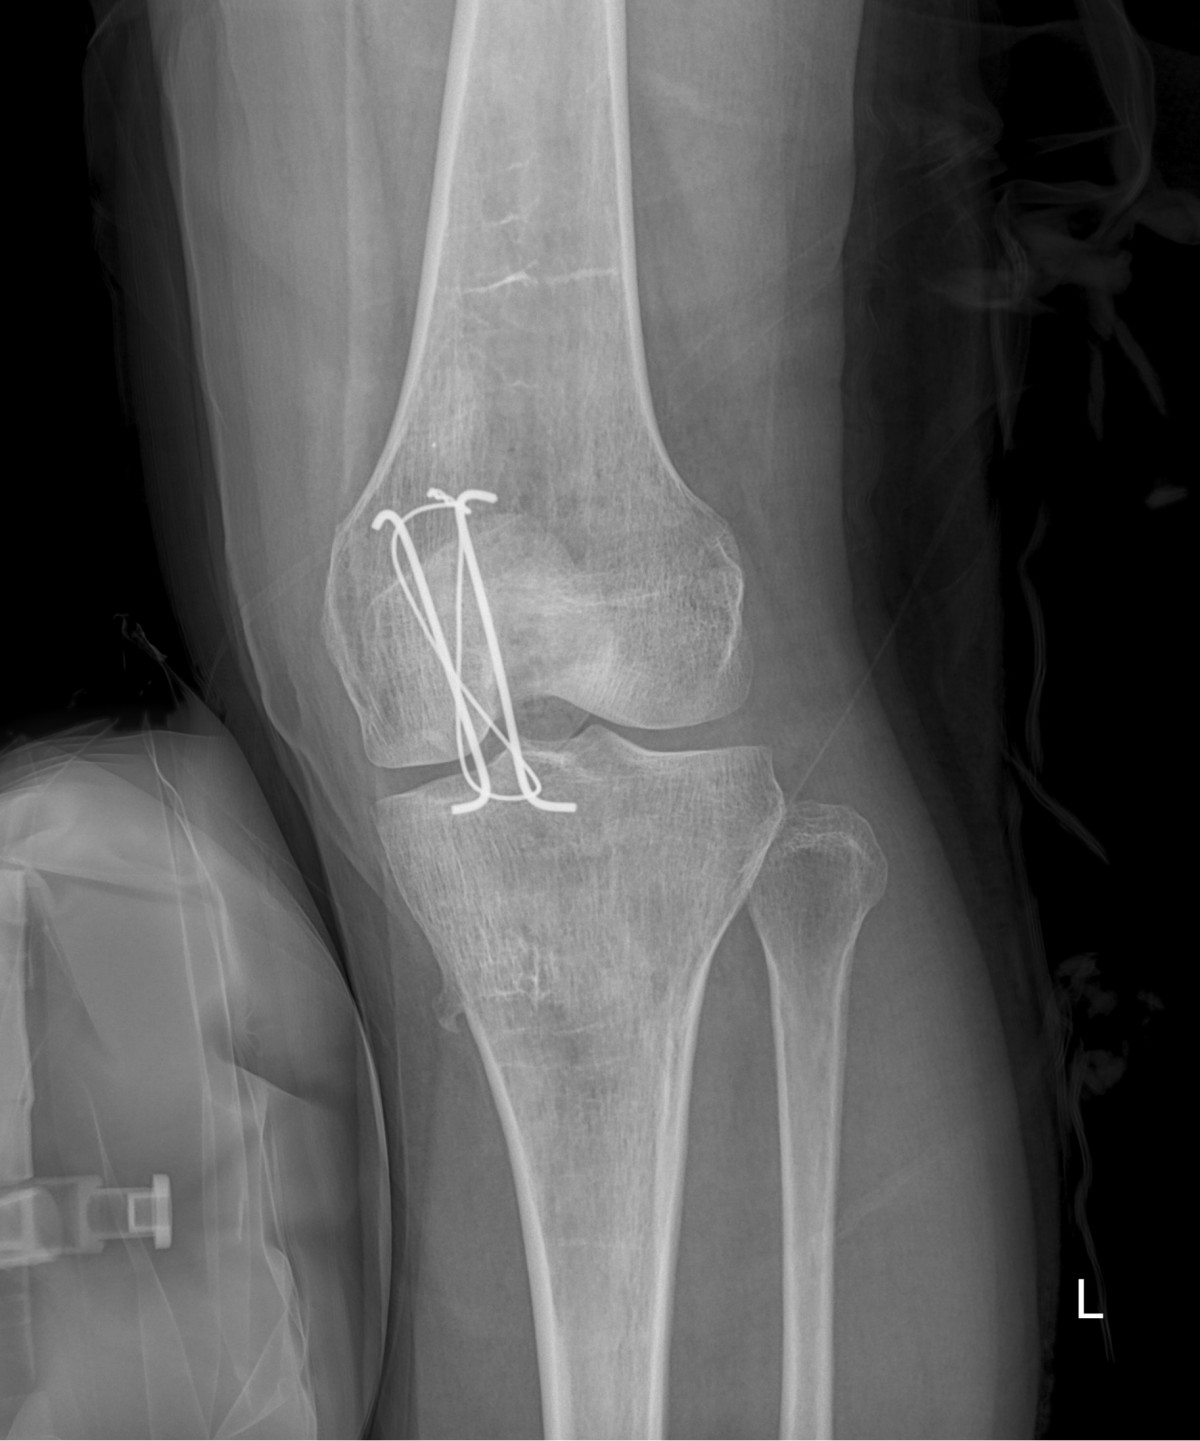

이재상원장님 무릎 골절 수술 고현O 환자

dae765e4d9ac96aee867c9d6292d8784_1758001579_6641.jpg